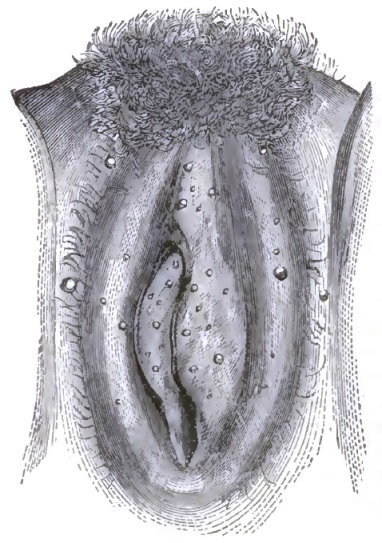

| 28. | FOLLICULAR VULVITIS (HUGINER) |